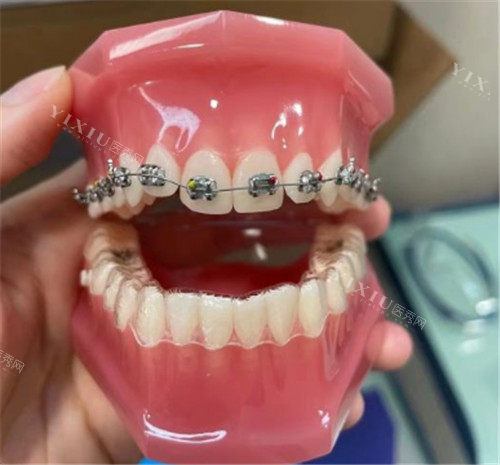

金属托槽矫正是一种传统且常见的矫正方式,其价格相对较为亲民。在大冶地区,金属托槽矫正的价格范围大致在5980元至15000元之间。

基础款的金属托槽矫正价格通常在5980元起,这类矫正方式适合对价格较为敏感、牙齿畸形程度相对较轻的患者。它的优点是技术成熟,矫正力量稳定,能够满足大多数牙齿排列不齐患者的矫正需求。不过,金属托槽矫正也存在一些缺点,比如金属托槽较为显眼,美观度欠佳,而且在矫正过程中,由于托槽和弓丝之间存在较多缝隙,口腔清洁难度较大,若清洁不深度,容易残留食物残渣,引发龋齿、牙周炎等问题。

对于一些牙齿畸形程度较复杂,或者对矫正效率有更高要求的患者,可能会选择价格稍高的金属托槽矫正方案,价格上限可达15000元左右。这些方案可能会采用更优质的金属材料,或者结合一些个性化的矫正设计,以提高矫正的结果和舒适度。